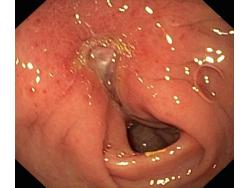

Wrzód trawienny